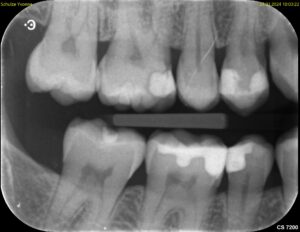

Die Aufnahme dauert nur Sekundenbruchteile. Da der Sensor nah am Zahn liegt und der Röntgenstrahl gezielt auf einen kleinen Bereich gerichtet ist, liefert der Zahnfilm eine deutlich höhere Detailschärfe als das OPG (Orthopantomogramm). Feine Strukturen wie beginnende Karies, Wurzelkanäle oder der exakte Verlauf des Knochens an einzelnen Zähnen lassen sich präziser beurteilen.

Typische Einsatzgebiete sind die Kariesdiagnostik (besonders die sogenannten Bissflügelaufnahmen für die Zahnzwischenräume),

Die Beurteilung von Wurzelkanalfüllungen, der Verdacht auf Wurzelspitzenentzündungen, die Kontrolle nach Zahnentfernungen oder Implantationen sowie die genaue Darstellung des Knochenabbaus bei Parodontitis. Ein vollständiger Röntgenstatus aus 10 bis 14 Zahnfilmen zeigt das gesamte Gebiss in hoher Auflösung, wird aber wegen des höheren Aufwands nicht routinemäßig angefertigt.